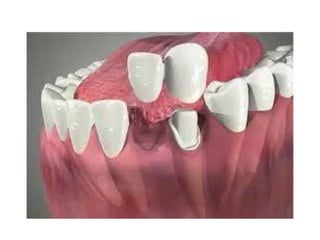

* Implant supported fixed

prosthesis: are surgically placed

implant within bone and projected

though the mucosa, on which the

abutment are screw retained , fixed

partial denture the constructed on

the abutment